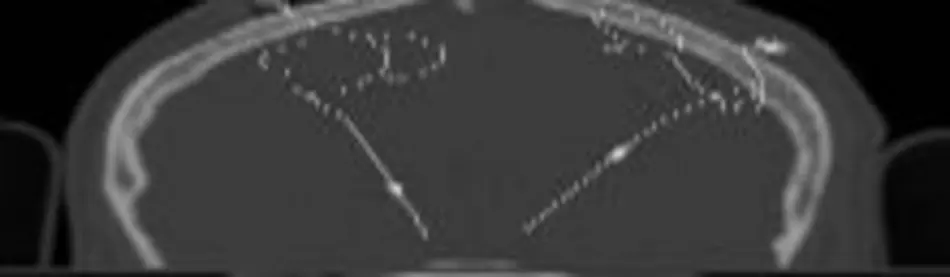

Es kann daher nicht davon ausgegangen werde, dass nach der OP die berechneten Koordinaten mit den tatsächlichen übereinstimmen. Eine Möglichkeit der Elektrodenlokalisation ist die Verwendung von postoperativen CT-Aufnahmen. Wegen der metallischen Natur der Elektroden treten allerdings in diesen Tomografien Artefakte auf, die eine einfache visuelle Lokalisation erschweren.

• LIS-Verfahren: Das Line-Intersection-Verfahren basiert auf der Analyse der Linienartefakte, die in den angefertigten CT-Aufnahmen aufgrund der nahezu totalen Absorbtion von Röntgenstrahlen durch die metallenen Elektroden sowie durch den CT-Rekonstruktionsprozess entstehen. Mit Bildverarbeitungsmethoden werden die Linienartefakte segmentiert und die extrahierten Linien geschnitten.

• COG-Verfahren: Das Center-Of-Gravity-Verfahren nutzt die runden bis ellipsenförmigen Elektrodenartefakte die sich um den Elektrodenmittelpunkt bilden. Die Artefakte werden anhand hoher Grauwerte segmentiert und der Schwerpunkt ermittelt